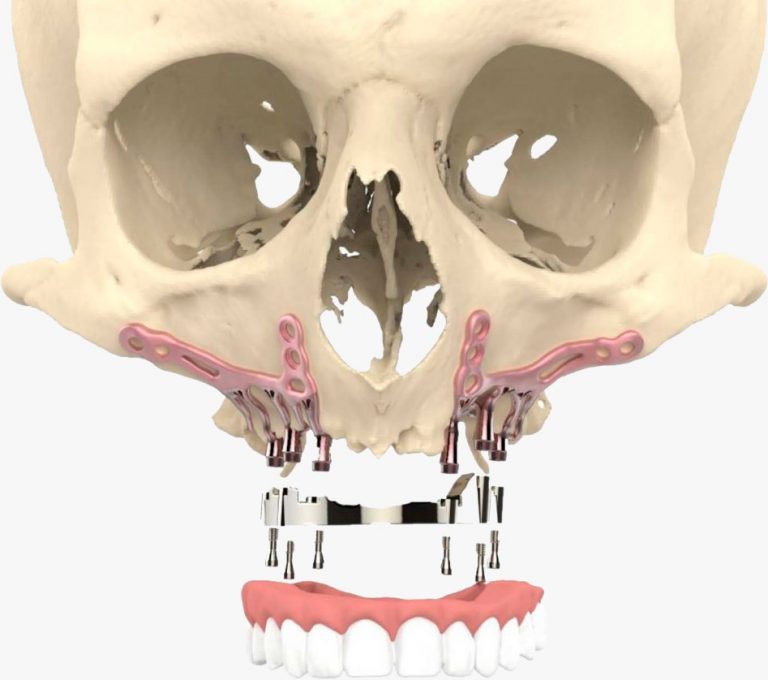

Los implantes subperiósticos son dispositivos diseñados para colocarse sobre el hueso maxilar o mandibular, justo debajo del tejido gingival. A diferencia de los implantes tradicionales, que se integran directamente en el hueso, esta técnica es especialmente útil para pacientes que presentan pérdida ósea significativa y no pueden someterse a un injerto óseo previo.

El diseño del implante es personalizado, utilizando tecnología avanzada como escáneres 3D para garantizar un ajuste perfecto a la anatomía del paciente.

Se realiza un escáner 3D de la zona para diseñar el implante personalizado.

Con los datos obtenidos, se crea un modelo exacto del implante para garantizar su adaptación.

En una intervención mínimamente invasiva, el implante se fija al hueso bajo el tejido gingival.